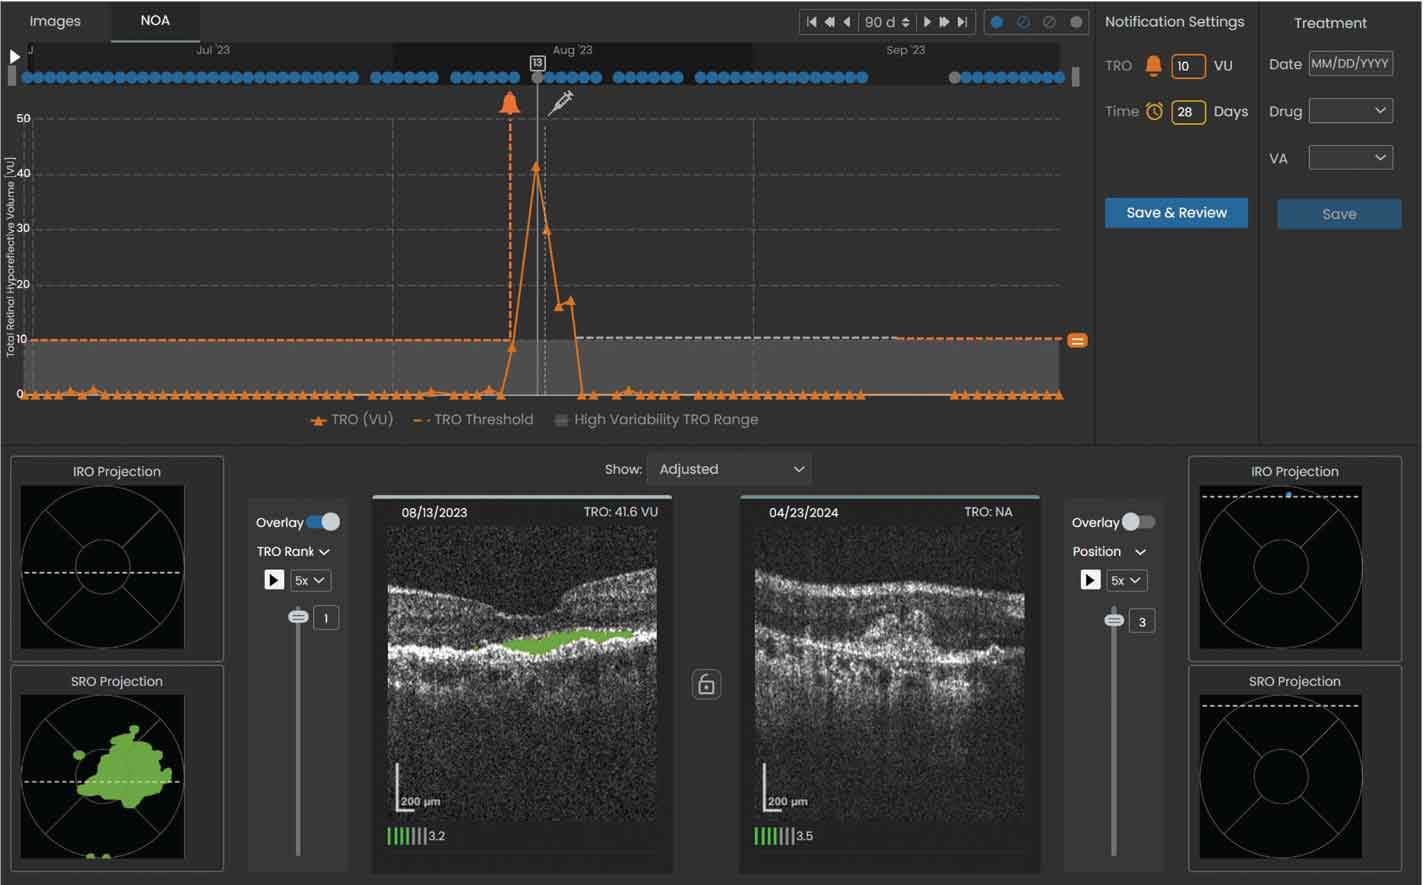

Figure 3. Sample volume trendline showing a notification was sent to the reviewing physician when the total retinal volume crossed the set threshold of 10 µL. The left OCT scan shows the total retinal volume reached a maximum of 41.6 µL within the specified 90-day window on 08/13/2023 and was predominantly SRF (denoted by the shaded green area). |

5. If fluid volume or the time interval exceeds the set threshold (Figures 3 and 4), a notification will prompt review by the retina specialist, and the patient may subsequently be scheduled for an in-office evaluation and injection visit.